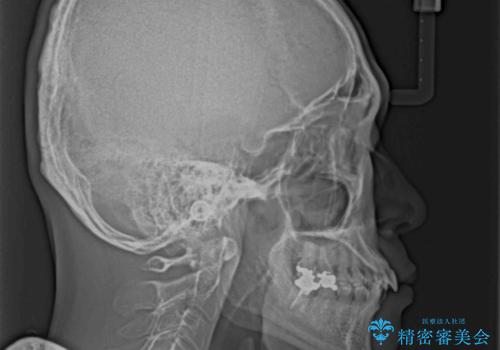

強い咬合力と上顎前歯の傾斜により前歯が突出し、唇が閉じにくい状況であったため、上下左右の第一小臼歯4本を抜歯し、ワイヤー装置にて矯正治療を行うこととしました。

非常に咬合力が強いため、抜歯したスペースが閉じるのか不安でしたが、順調に歯が移動し、予定よりも早く治療を終えることができました。